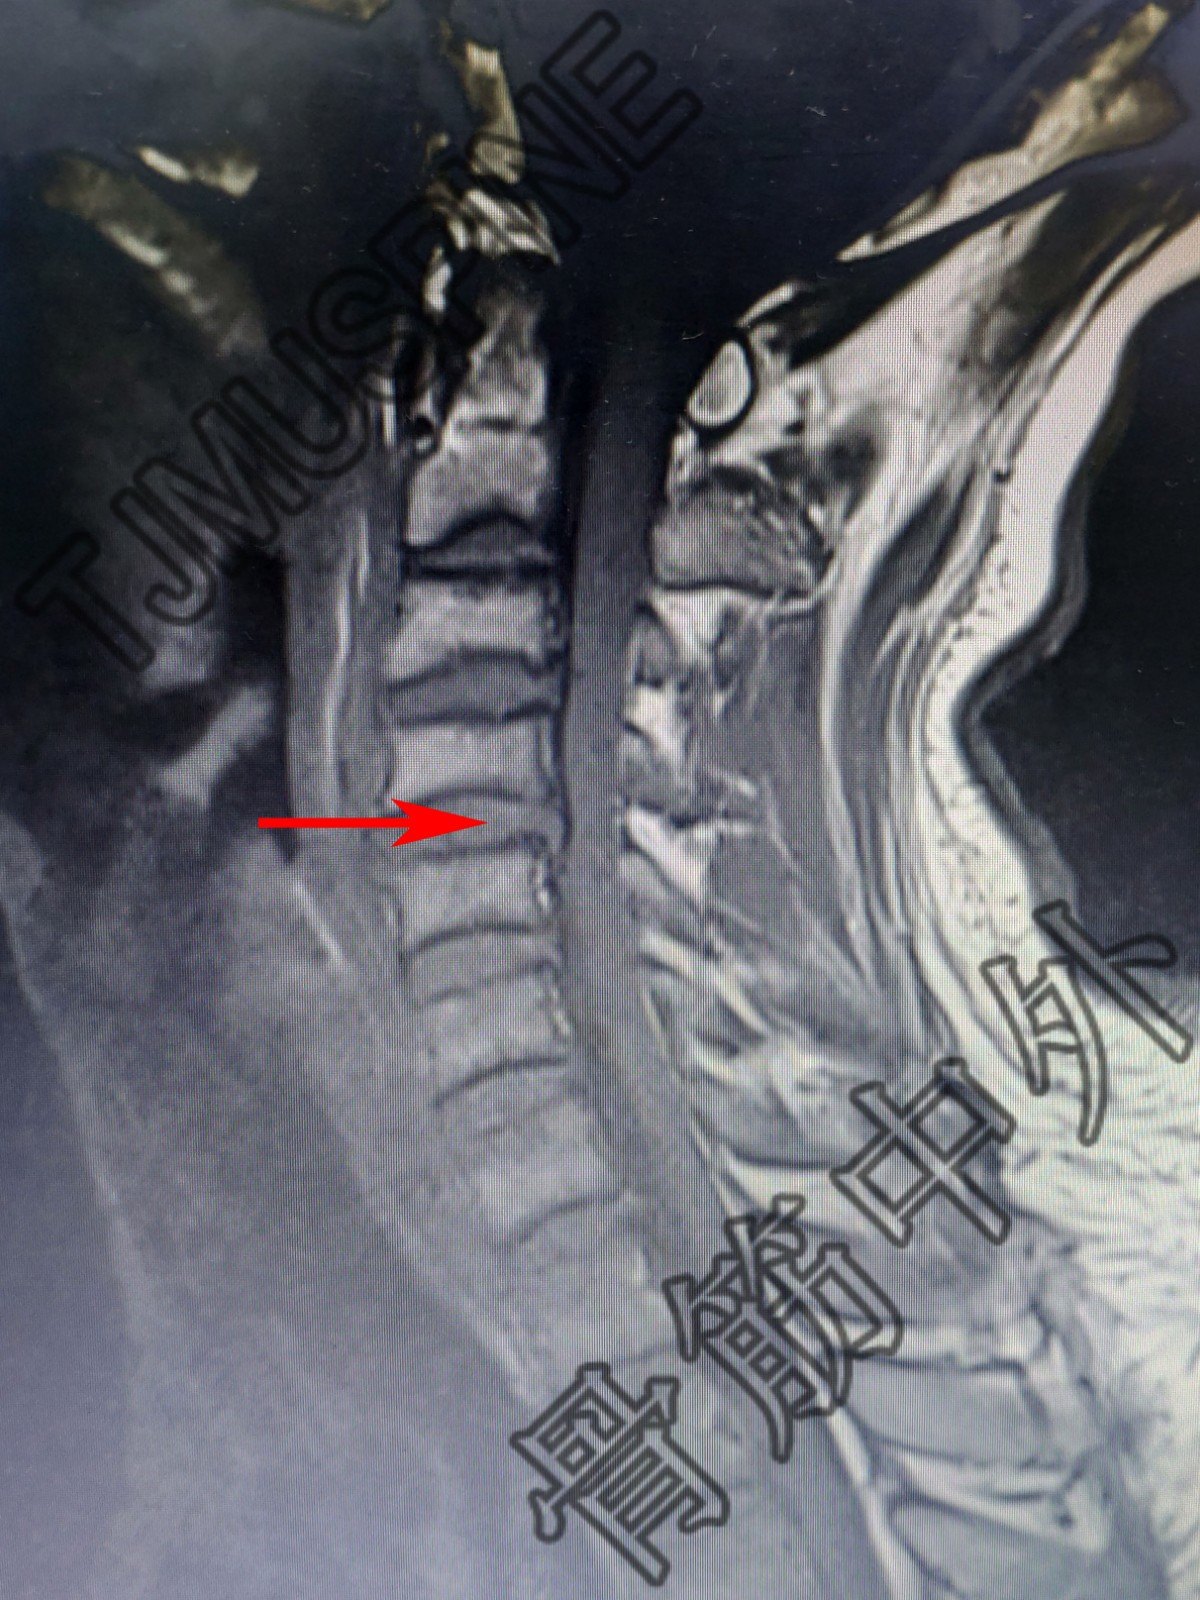

c6/7椎间盘向正后方突出,相邻硬膜囊受压,椎管前后径未见变窄.

4/5.5/6c6/7均有不同程度的间盘膨出,硬膜囊受压现象

颈5,6硬膜囊受压.